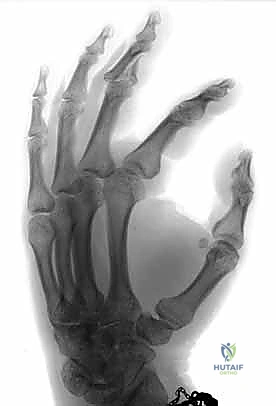

معرض الصور الشعاعية: رحلة الشفاء من الكسر إلى التعافي

لفهم مدى فعالية هذه التقنية، دعونا نستعرض سلسلة من الصور الشعاعية لحالات حقيقية ومعقدة، توضح حالة المفصل قبل التدخل، أثناء الجراحة، وبعد الالتئام التام.